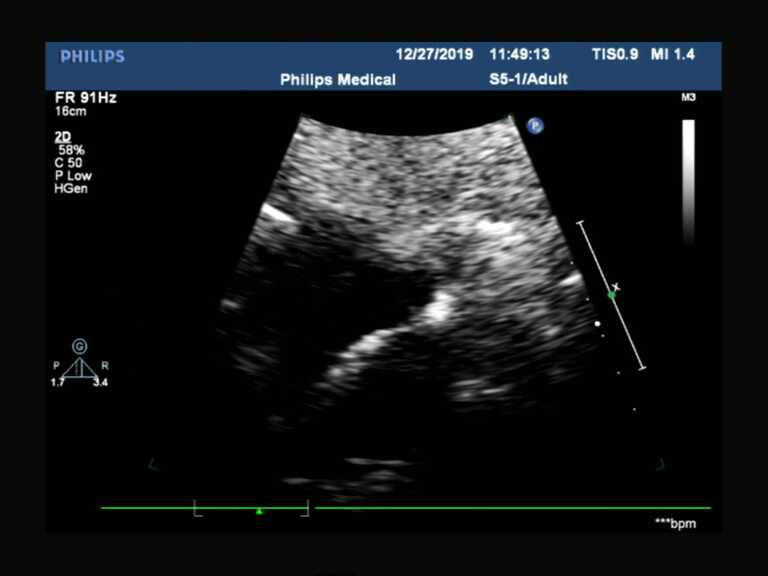

图片2.png

图二:仅见点滴状红色过隔血流信号

图一、图二高度怀疑卵圆孔未闭,结合临床表现(如不明原因头疼、青年人群的腔梗),建议经食管超声心动图和右心声学造影,下图为此患者诊断卵圆孔未闭提供了进一步的依据(右心声学造影见右向左大量微气泡)